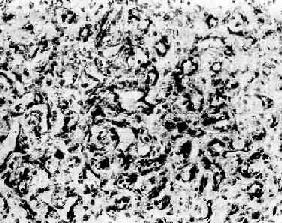

图7-15 纤维瘤

瘤组织由分化良好的纤维细胞构成,呈编织状排列,有丰富的胶原纤维